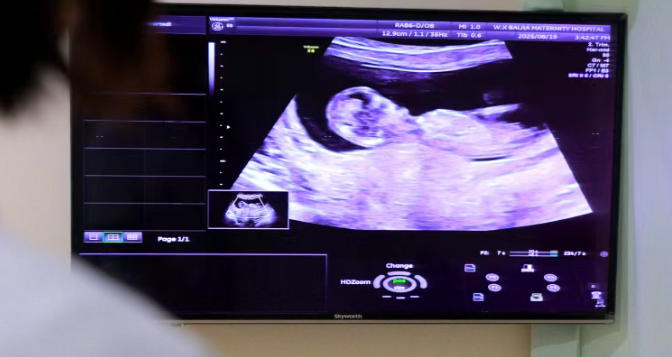

NT检查是通过B超手段测量胎儿颈项部皮下无回声透明层较厚的部位,用于评估胎儿是否有染色体异常。

NT检查通常在孕11~13周+6天进行。11周之前扫描从技术上来讲很困难,因为胎儿太小,而过了14周,过多的液体可能被胎儿正在发育的淋巴系统吸收,结果不准确。